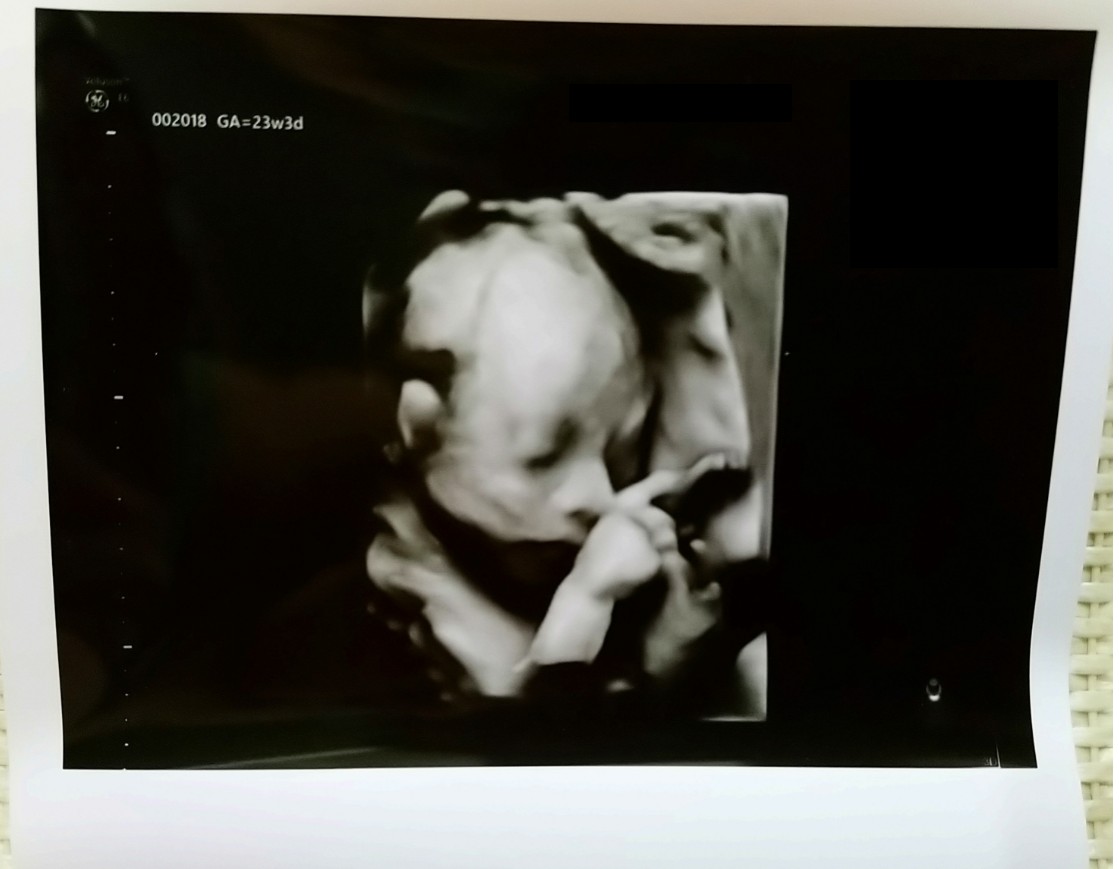

5.開始照超音波,幫我檢查的是位女醫師,醫師詳細的告知現在照的是寶寶哪個部位,這個部位的狀況,有些部位會看流血狀況,我有印象是照了:大腦、心臟、胃、腎、手(手臂,手指)、腳(大腿,小腿,腳指)、臉(眼睛, 鼻子, 嘴巴, 耳朵),照完目前寶寶的狀況是ok(醫師印出寶寶一張比ya的超音波照片,給我們留做紀念[寶寶人生第一次拍沙龍照]),報告會送回原產檢診所,再由產檢醫生說明報告內容。